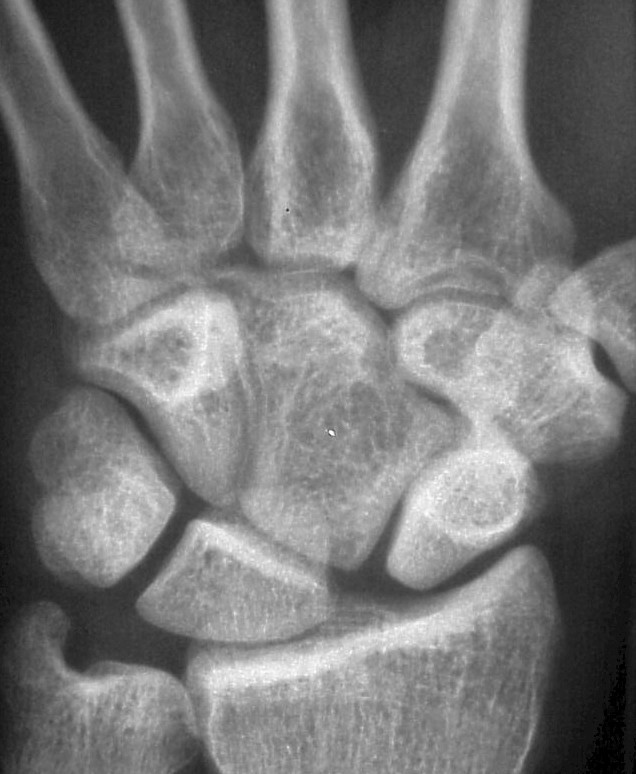

Radial and ulnar deviation views show minimal additional scapholunate widening in ulnar deviation.